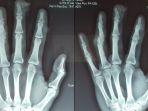

"Tiga jari saya mengalami luka. Paling parah adalah jari manis yang tulangnya remuk, sedangkan jari tengah ujung tulangnya hancur," kata Adit

Seorang warga Donomulyo, Novi Fransiska Aditama, mengaku menjadi korban penganiayaan pemilik Triangle Cafe and Beer House, Kota Malang, berinisial J.

Bos Triangle Cafe and Beer House, Jhonson dilaporkan oleh pegawainya, Novi Fransiska Aditama.

Kasus sadis, atasan pukulkan palu ke tiga jari anak buah di Triangle Cafe and Beer House, Kota Malang.